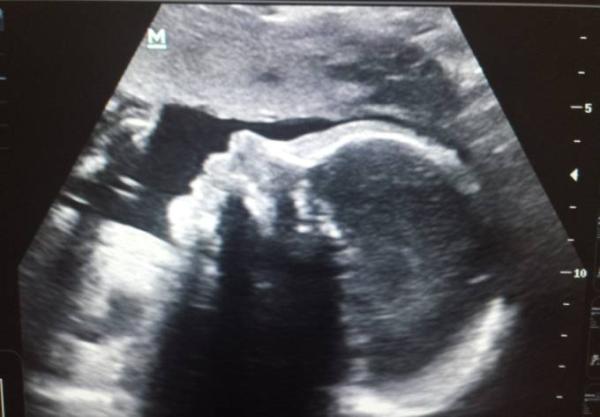

Hallo ihr Lieben. Hatte heute auch mein letzten großen Ultraschall. Wow 1340g und 39cm ist der kleine Mann schon groß Das CTG hat er fast verschlafen und ich hab nur 1 kg zugenommen seit dem letzten Termin hätte auf mehr getippt bin jetzt bei + 8kg, hab aber auch mit 74 kg angefangen ;)

Han des Bild ganz vergessen

Bild zu

Was für ein hübsches Bild. Schön das es den Zwerg so gut geht. Nur 8 Kilo. Ein Traum.

Schön dass alles gut ist. So ein schönes Bild